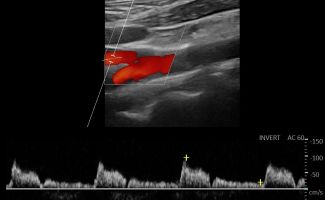

- Έγχρωμο Doppler: Αξιολογεί την ταχύτητα και την κατεύθυνση της ροής του αίματος, προσδιορίζοντας την ύπαρξη και το ποσοστό στένωσης των αρτηριών.

- Παλμικό Doppler: Παρέχει πληροφορίες για τις διακυμάνσεις της ροής του αίματος, βοηθώντας στην αναγνώριση πιθανών αιμοδυναμικών διαταραχών.